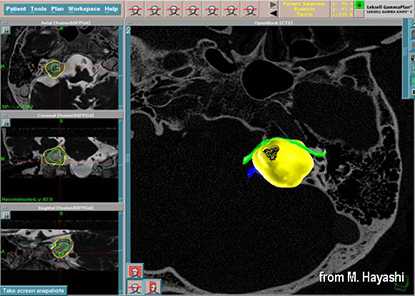

До начала радиохирургического лечения проводится обследование, позволяющее определить точное положение опухоли и прилегающих нервных образований. Выполняется трехмерная реконструкция, отображающая детальную микрохирургическую анатомию этой области. Для этой цели с помощью МРТ получают четкую визуализацию опухоли и нервов во внутреннем слуховом проходе и области мосто-мозжечкового угла.

С помощью планирующей системы Gamma Planи автоматической позиционирующей системывозможно проводить очень точное облучение опухоли (точность 0,5 мм), избегаяповреждения черепных нервов и других важных отделов мозга.

Слева - МРТпациентки М., 65 лет. Обратилась в радиохирургический центр МИБС с диагнозом-невринома правого VIII нерва. Проведено радиохирургическое лечение, доза по краю невриномы составила 13 Грей, в изоцентре опухоли 21,7 Грей.

Справа - контрольное МРТ через 1,5 года после операции. Отмечается уменьшение объёма опухоли на 47%.